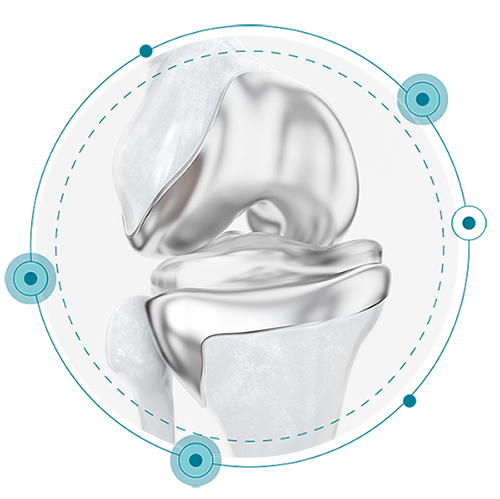

Un paciente. Un implante

Ajuste individualizado

que prácticamente elimina las dolencias ocasionadas en pacientes con otro tipo de prótesis de rodilla.

Consigue una sensación más natural

Prótesis de rodilla 3D está diseñada para seguir la forma y el contorno de la rodilla de cada paciente, proporcionando un mayor potencial para su rodilla con una sensación más natural.

Evita la inestabilidad

Mantiene las líneas naturales de la articulación del paciente para evitar la inestabilidad, causa común de la insatisfacción del paciente.